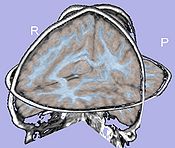

- 1.5. Cortical thickness computation

- Asymmetric cortical thickness on label map

- Tool: CortThick (UNC Slicer3 external module)

- 1.8. Cortical thickness attribute computation

- Cortical thickness interpolation on genus-zero surface

- Tools: MeshCortThick, MeshMath (UNC Slicer3 external modules)